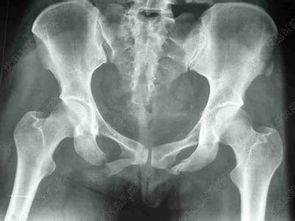

1外傷引起的紋狀骨折,就是說在X線上可以看到骨折線,但是沒有明顯的錯位,外觀上也沒有明顯的畸形和腫脹,這種情況一般都可以采取直接固定的辦法,比如夾板、石膏、腳套等各種固定用品。再就是錯位不嚴(yán)重的骨折,比如柯氏骨折、史密斯骨折,可以通過手法復(fù)位后石膏固定,復(fù)位后復(fù)查X線,如果對位對線良好就OK,一個月左右就可以取下石膏。還有就是錯位嚴(yán)重的、手法復(fù)位不能成功的和粉碎性的骨折,這種骨折一般都需要手術(shù)治療,清除碎骨片后根據(jù)情況使用鋼釘或者鈦板固定,手術(shù)后不必再使用石膏固定。在藥物上很簡單,一般就是營養(yǎng)骨細(xì)胞的藥物,比如骨肽注射液等,有傷口的要使用消炎藥。